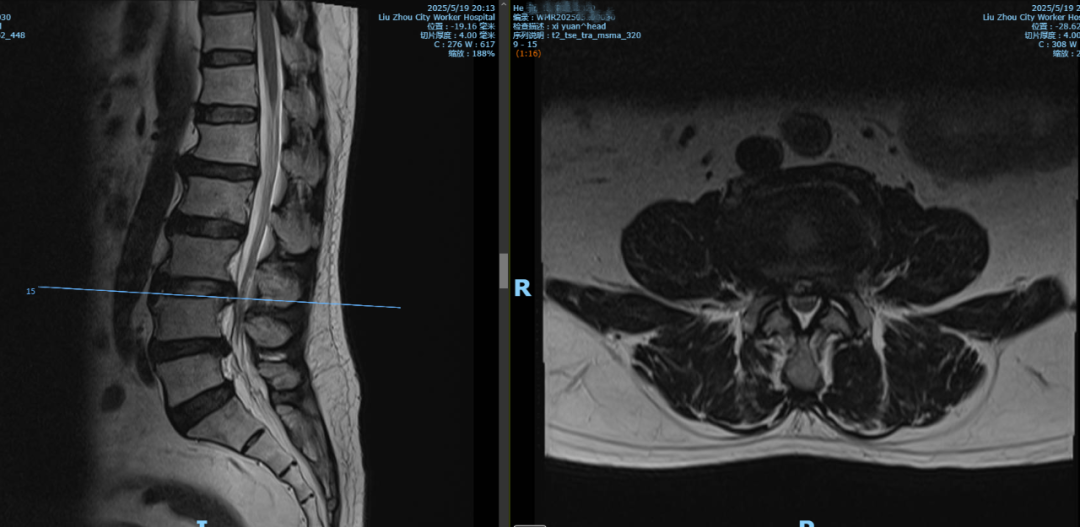

何先生今年65岁,患有脑梗、冠心病、高血压病等多种基础病,特别是腰腿痛多年,两个月前腰痛伴左下肢疼痛剧烈,弯腰时症状明显,到外院就诊被诊断为“L3/4、L4/5腰椎间盘突出”。

由于何先生患有多种基础病,病情复杂,手术风险巨大,辗转多家医院,均未能解决问题。经朋友介绍,近日,何先生在家属陪伴下来到柳州市工人医院西院(柳州市骨科医院)脊柱外科就诊。脊柱外科主任彭小忠接诊后,诊断患者有腰椎间盘突出、腰椎失稳、冠状动脉粥样硬化、高血压、脂肪肝、脑梗死,双眼白内障、青光眼,头颅、颈椎椎动脉狭窄还放置有血管支架。

患者术前影像资料显示,L3/4、L4/5腰椎间盘突出并腰椎不稳